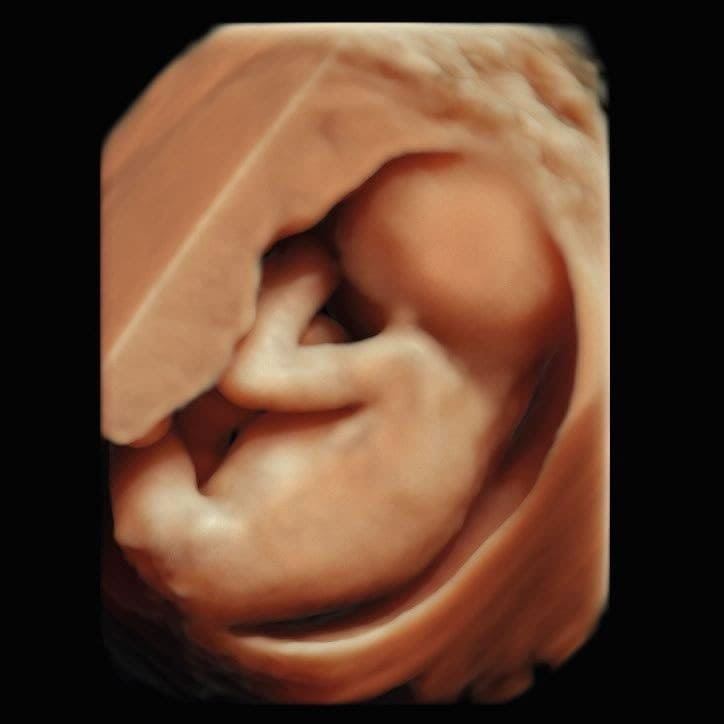

Im ersten Trimenon (1. Schwangerschaftsdrittel) bieten wir Ihnen verschiedene Untersuchungen an. Ab der 12. SSW können unter anderem bereits Kopf, Herz und Extremitäten untersucht und einige Fehlbildungen ausgeschlossen werden.

Im Ersttrimesterscreening (12-14 SSW) können wir durch Messen der Nackentransparenz, Darstellung des Nasenbeins und weitere Parameter zusätzlich das Risiko für Chromosomenstörungen bei Ihrem Kind ermitteln.